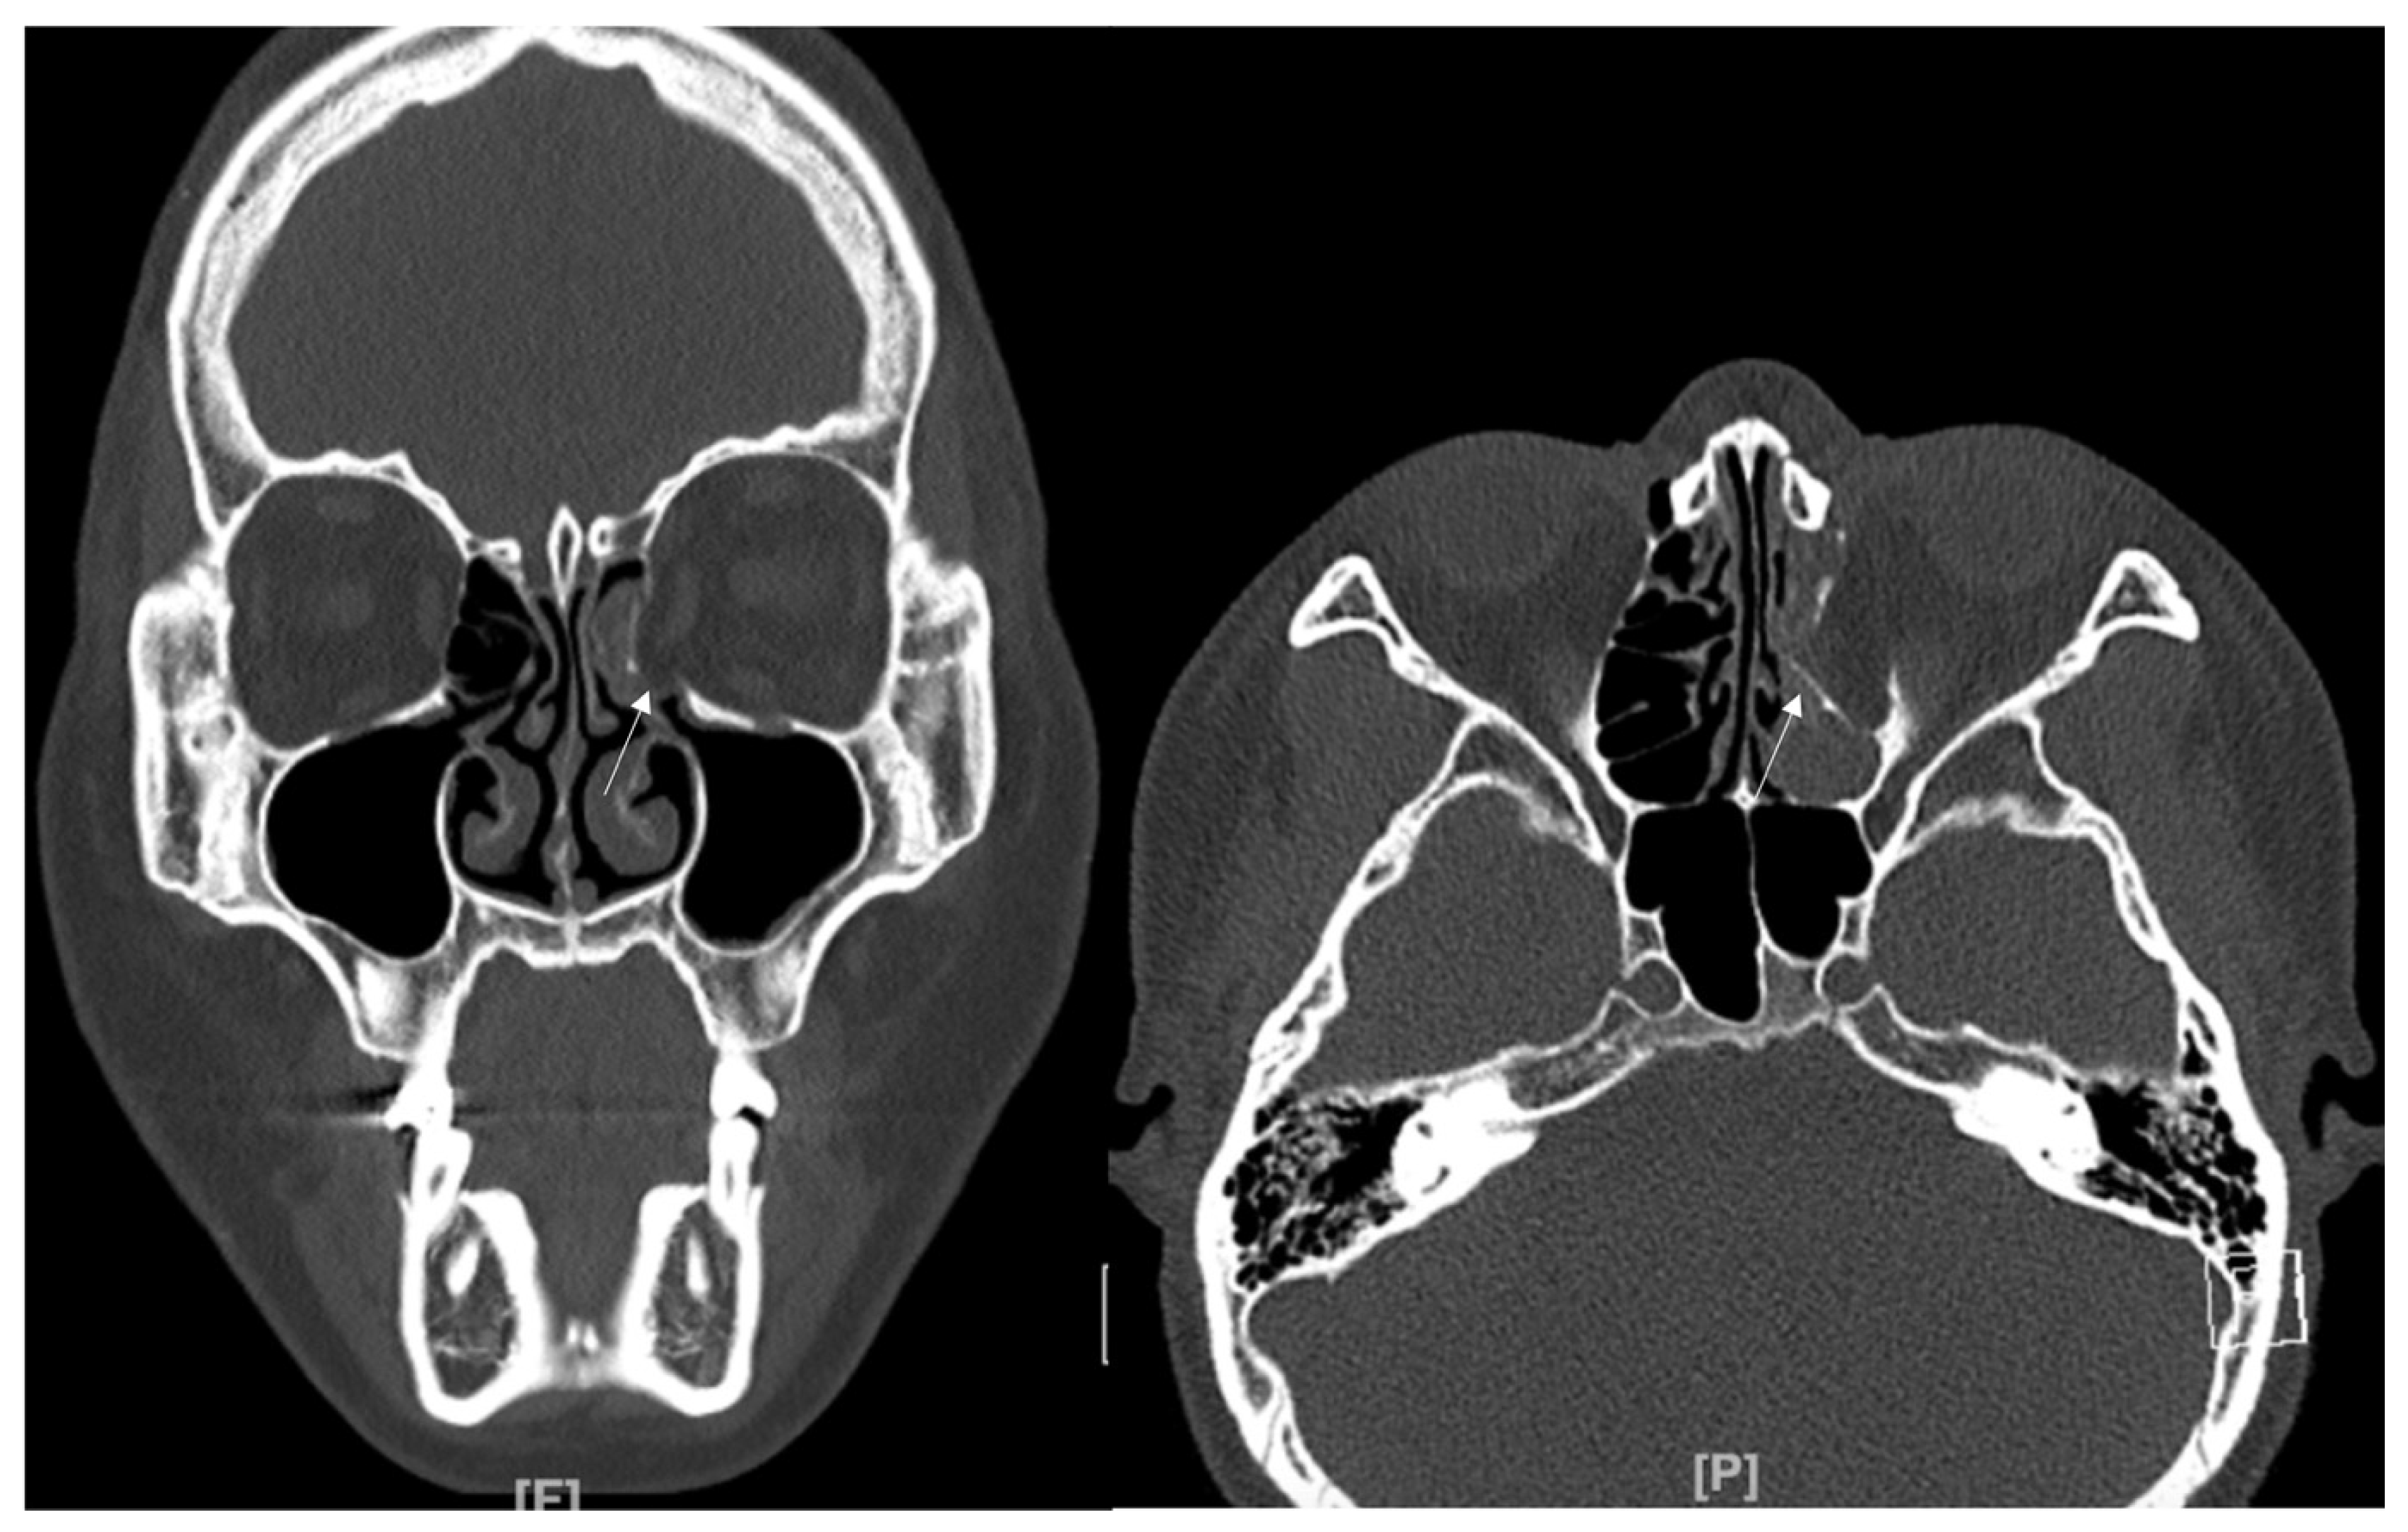

An 8-year-old boy came to our emergency room with nausea, vomiting, bradycardia, and lethargy following a left eyeball trauma hit by a baseball. The patient complained of severe pain and discomfort with eyeball movement (Figure 1). We surgically approached the inferomedial orbital wall fracture on the same day of the trauma. After the subciliary incision, the fracture was exposed. The titanium-reinforced porous polyethylene (TR-PPE) plate was placed on the fracture site using a single screw at the inferior orbital rim (Figure 2). The oculocardiac reflex was entirely gone immediately after surgery. The patient was discharged on postoperative day 2 with significantly improved pain and discomfort.

Figure 1. Case 1. Preoperative facial CT scan (coronal view) of the 8-year-old male patient with left inferomedial orbital wall fracture. The fracture sites were designated with white arrows.